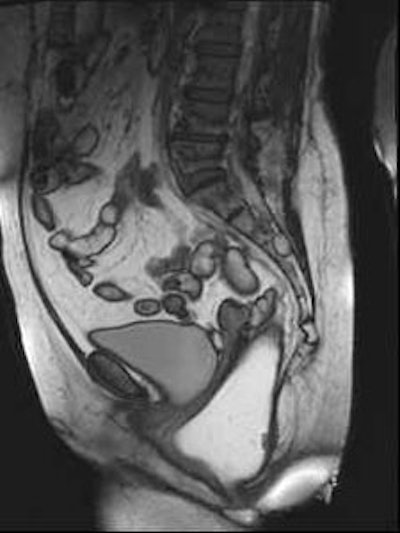

Sagittal late evacuation view shows a cystocele in the middle and posterior pelvic floor compartment. Image courtesy of Dr. Steve Halligan.